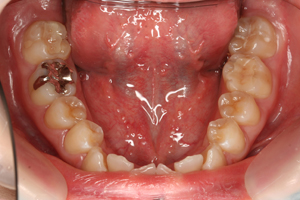

セット後

これで健康的な口元になり、大きく口を開けて笑った写真も気になりません。